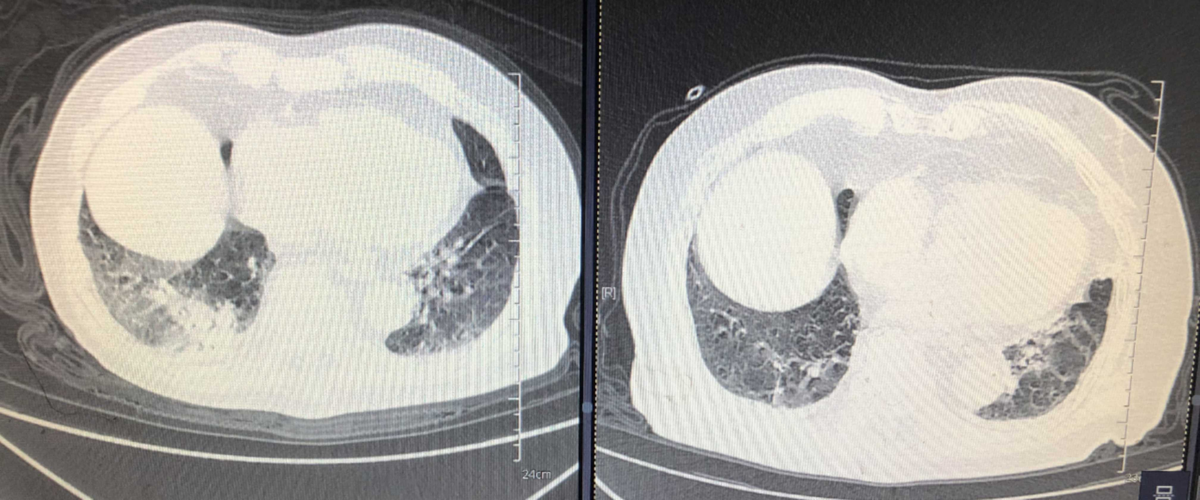

入院后,医生马上为徐嗲嗲完善各项检查,肺部CT显示他有60%-70%“白肺”,肺部病变严重,血氧饱和度也仅有71.2%。针对徐嗲嗲严重缺氧的情况,医生指导他进行俯卧位通气并给予心脏药物治疗,帮助他提升血氧饱和度。由于肺部大部分面积变白,徐嗲嗲还是面临着是否要转入ICU插管的抉择。

“大部分患者都是老年人,且高龄老人不少”,94岁高龄的王嗲嗲是呼吸与危重症医学科这一个月以来收治的年龄最大的新冠患者。2023年1月2日入院后,医生对王嗲嗲进行了评估:一型呼吸衰竭、病毒性肺炎,肺部CT显示60%-70%白肺,血氧饱和度80%,当时的王嗲嗲甚至都没有办法正常交流。从家属处得知,王嗲嗲还有肾功能不全、脑梗塞病史。医生立即对王嗲嗲采取鼻导管+面罩吸氧以及抗凝药物和抗病毒药物治疗,同时两小时换一次高侧卧位通气。

1月13日,高侧卧位躺在病床上的王嗲嗲正在休息,床旁的生命体征监测仪指标显示良好。王嗲嗲的责任医生卢俊娟欣慰地说:“王嗲嗲的血氧饱和度在吸氧的状况下已经能维持在95%以上,CT显示肺部感染病灶也已经逐渐吸收,再稳定两天就可以考虑出院了。”